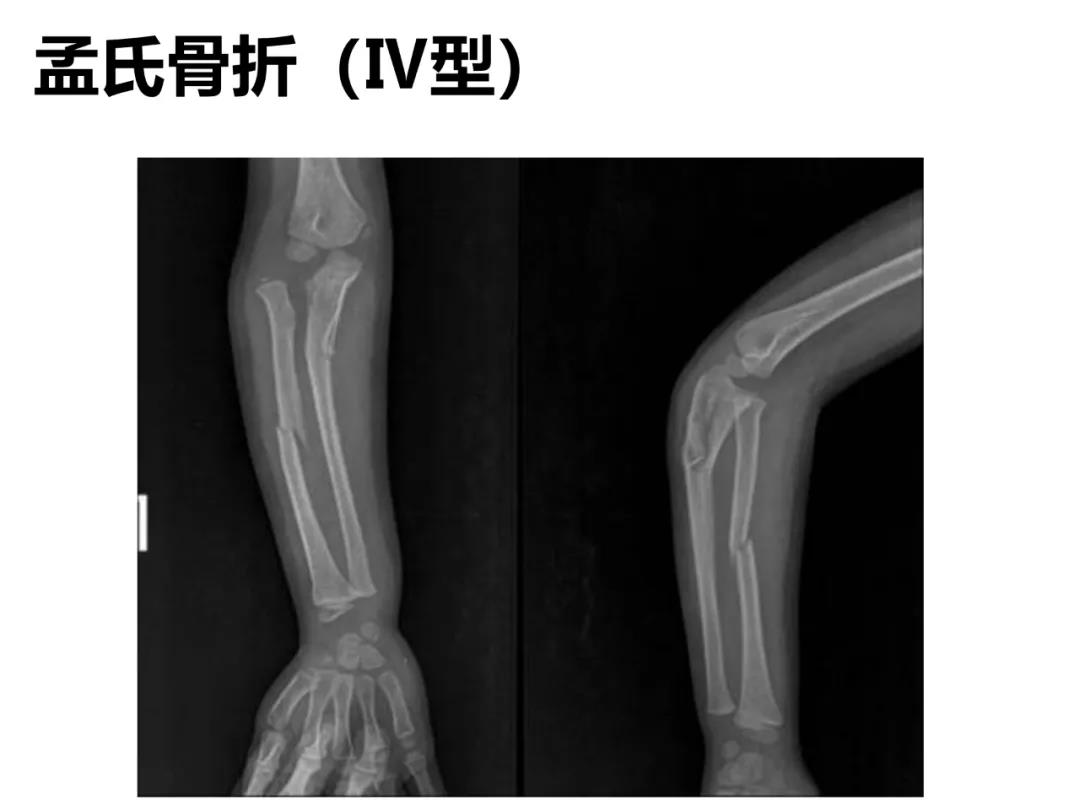

小儿骨科X线片汇总,临床读片宝典!